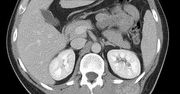

Guzy można łatwo zdiagnozować poprzez badanie USG - są na nich bardzo wyraźnie widoczne. Ich leczenie, w zależności od stopnia złośliwości, polega na wycięciu zmiany i zastosowaniu chemioterapii lub radioterapii. Metoda leczenia powinna być indywidualnie dobrana do rodzaju nowotworu i stanu zdrowia pacjenta.